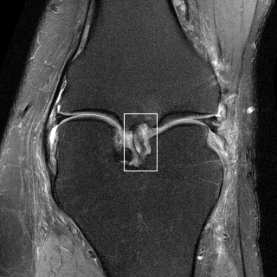

Deep Learning (DL) methods have shown promising results for solving ill-posed inverse problems such as MR image reconstruction from undersampled $k$-space data. However, these approaches currently have no guarantees for reconstruction quality and the reliability of such algorithms is only poorly understood. Adversarial attacks offer a valuable tool to understand possible failure modes and worst case performance of DL-based reconstruction algorithms. In this paper we describe adversarial attacks on multi-coil $k$-space measurements and evaluate them on the recently proposed E2E-VarNet and a simpler UNet-based model. In contrast to prior work, the attacks are targeted to specifically alter diagnostically relevant regions. Using two realistic attack models (adversarial $k$-space noise and adversarial rotations) we are able to show that current state-of-the-art DL-based reconstruction algorithms are indeed sensitive to such perturbations to a degree where relevant diagnostic information may be lost. Surprisingly, in our experiments the UNet and the more sophisticated E2E-VarNet were similarly sensitive to such attacks. Our findings add further to the evidence that caution must be exercised as DL-based methods move closer to clinical practice.